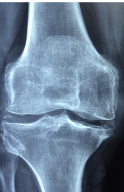

다리 관절 통증의 원인은 다양합니다. 대표적인 원인은 다음과 같습니다.

- 골관절염: 다리 관절에 염증이 생기는 골관절염이 원인 중 하나입니다. 다리 관절의 연골 파괴, 관절염성 육아종, 관절 류마티스, 감염성 관절염 등이 있습니다.

- 외상: 다리 관절에 외상이 가해지는 경우가 있습니다. 스포츠 부상이나 교통사고 등으로 발생하는 외상은 다리 관절에 손상을 일으킬 수 있습니다.

- 과부하: 과도한 운동이나 일상생활에서의 과도한 사용으로 인해 다리 관절이 지나치게 사용될 경우 다리 관절 통증이 발생할 수 있습니다.

- 퇴행성 변화: 노화로 인한 연골 변화, 유전적 요인, 비만 등으로 인해 다리 관절 통증이 발생할 수 있습니다.

- 요통: 요통으로 인해 다리의 균형이 깨지면 다리 관절에 부하가 걸려 다리 관절 통증이 발생할 수 있습니다.

- 신경병증: 척추 디스크나 척추 협착증 등 신경병증으로 인해 다리 관절 통증이 발생할 수 있습니다.

- 기타: 근육통, 근막통증 증후군, 혈관 질환 등 기타 원인으로 인해 다리 관절 통증이 발생할 수 있습니다.

위와 같은 원인 중 하나 또는 복수 개의 원인으로 인해 다리 관절 통증이 발생할 수 있습니다. 따라서 다리 관절 통증이 발생하면 전문의를 방문하여 원인을 파악하고 치료받는 것이 중요합니다.